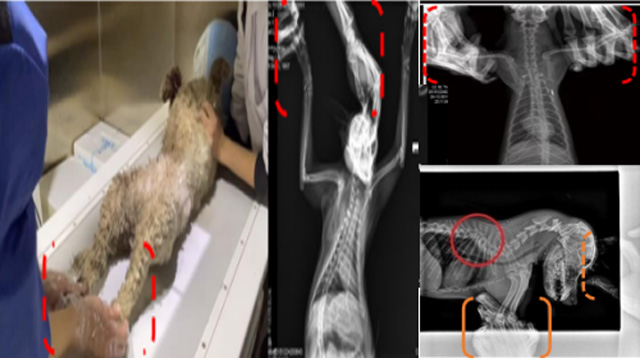

现在宠物医疗设备得到高速发展,现在有越来越多的宠物诊疗机构配置X射线装置如宠物DR。宠物骨折或者有其他疾病不能通过直观看出来的。宠物诊所医生都会使用宠物DR来做辅助检查。但是有时候宠物医生没有加强防护,就在宠物DR室给宠物拍X片做检查。这样也是会受到X射线的辐射。因为X射线上岗是属于职业病危害岗位。长期的辐射会对人体造成一定的危害。宠物医生也需要接受X射线照射的上岗前都必须进行放射工作人员的职业健康体检。体检不合格的话是不能担任放射工作的。未经上岗前职业健康体检的劳动者从事接触职业病危害作业的行为,已经违反了《中华人民共和国职业病防治法》第三十五条规定,依据《中华人民共和国职业病防治法》第七十五条规定,需要进行整改罚款??钩栉锓派湔锪苹疃谌粘9ぷ髦?,对本机构的X射线危害的职业病防治,需要知道并做到以下内容:

建造X射线机房时寻找专业防护施工队伍,对机房四方及上下方墙体进行屏蔽防护,尽可能隔室操作,使用铅防护门并安装工作指示灯张贴警示标识进行提醒。放射工作人员跟宠物主进入DR室需要穿戴铅衣、铅帽、铅手套等做好防护,减少X射线的辐射。避免暴露在照射范围中。宠物医生上岗前、在岗时、离开岗位时候的职业健康体检。如果检查异常就需要复查跟调离放射岗位。实施个人剂量监测和防护知识培训。并在劳动合同中向放射工作人员告知X射线危害相关内容。定期委托职业技术服务机构对机房防护、放射诊疗设备性能进行检测。不能忽略了对人的?;ぁ?/span>